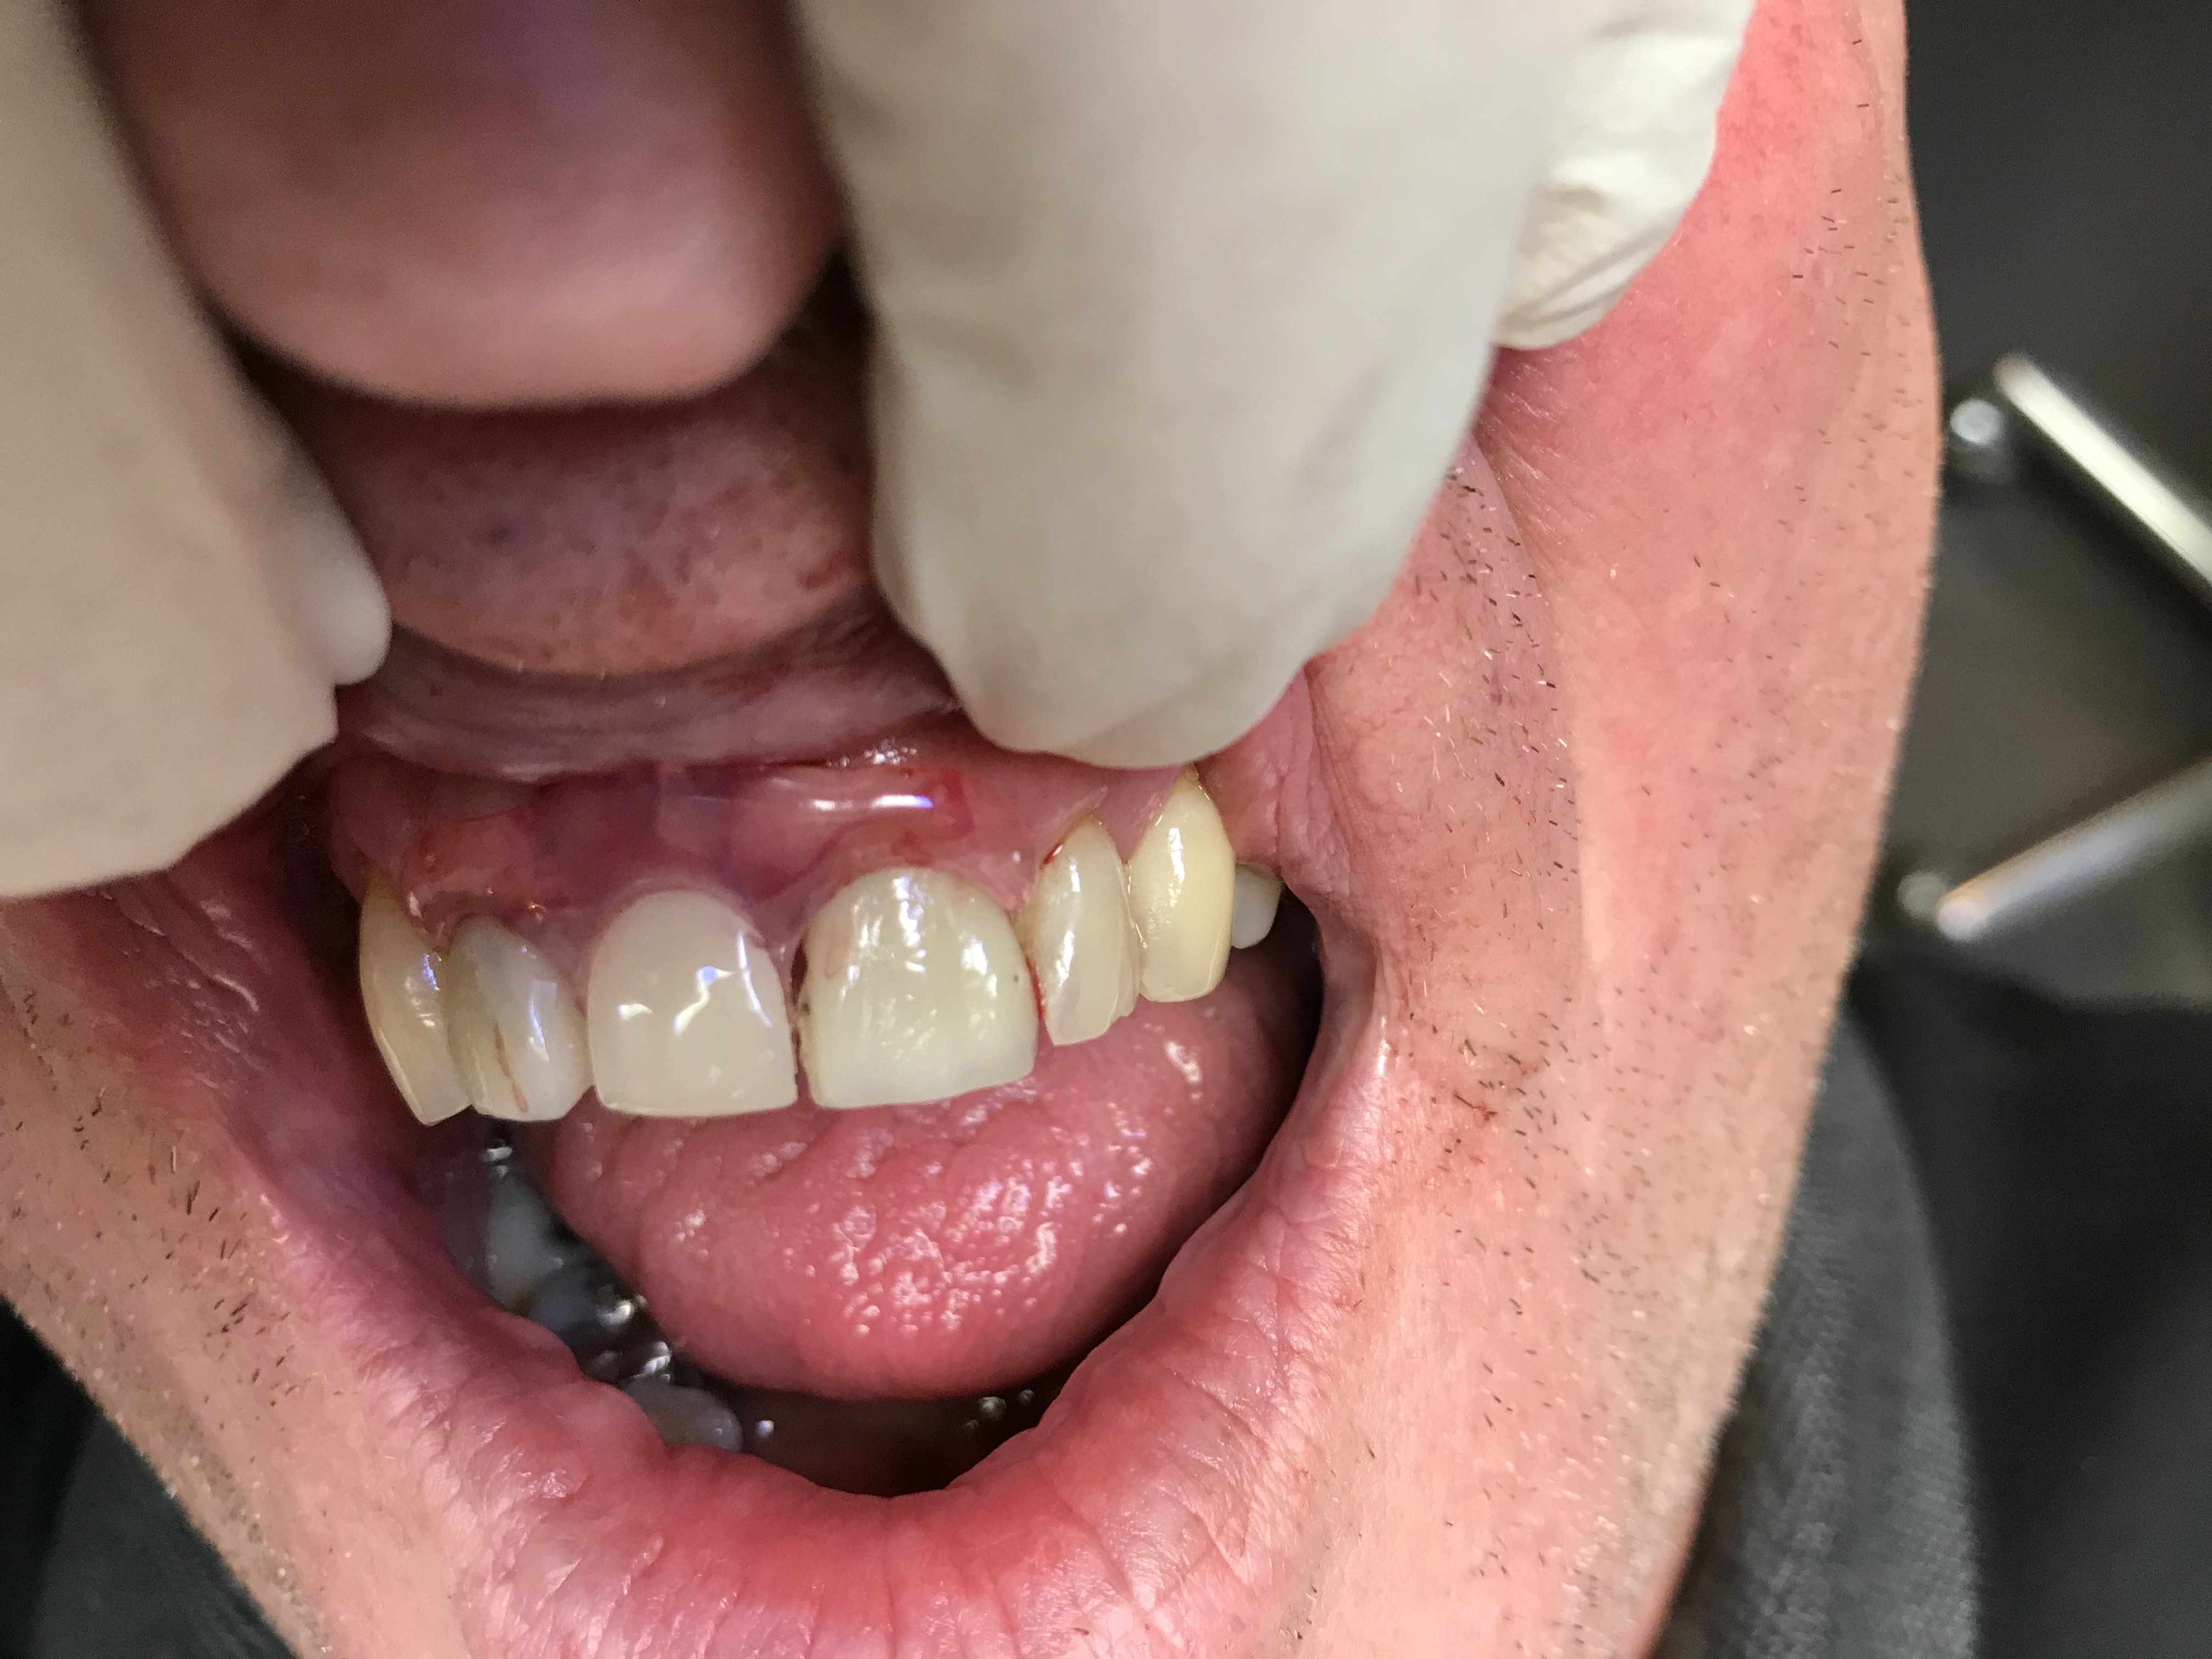

En fait c est un complet immediat suite a des extractions du bloc ant .

Et tu sais comme ils sont ces sto , ils te laissent des bosses de partout .

Du coup tout l os de devant est en contre depouille . D ou les crochets a os .

Enlaye tu trouves pas qu’en antérieur les bords sont fins ? Et que ça risque de blesser ? Ou alors il y a une subtilité qui m’échappe encore ??

Junior , bien obligé de faire fin devant sinon ça lui ferait une bouche de babouin .

non ,je ne met rien ,pas de fit ou de quoique ce soit . dans 3 semaines environ , je ferais un rebasage .

et si l'os me le permet je monterais devant .en attendant ,il faut gratter par ci par là .